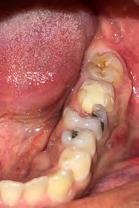

Paciente masculino de 23 años de edad el cual acudió al servicio de Odontología para valoración odon tológica anual como parte del exa men médico anual quien refiere a Cirugía Maxilofacial del Hospital Regional Naval de Acapulco (Figura 1). El paciente mencionó inicio de padecimiento con aumento de volu men y úlcera en paladar blando de 6 meses de evolución con salida de

material purulento (Figura 1). Negó crónico degenerativo, alérgicos y res to de antecedentes sin importancia. Se solicitaron estudios de laboratorio prequirúrgicos los cuales se encontra ron dentro de los parámetros norma les.

Estudios tomográficos en los cuales se observa tumoración expansiva a piso nasal de 3 centímetros de diá metro aproximadamente isodensa a tejidos blandos en zona de pala dar blando (Figura 3A y 3B). Motivo por el cual se decidió realizar biopsia incisional (Figura 4A , 4B y 4C) obte niendo un diagnóstico de Adenocar cinoma de células basales en paladar blando (Figura 5) con el cual se rea lizó referencia al centro oncológico naval para su seguimiento y trata miento. Actualmente se encuentra en tratamiento de quimioterapia.

Paciente Figura 1. Fotografía clínica frontal. Figura 2. Con aumento de volumen y úlcera en paladar blando.